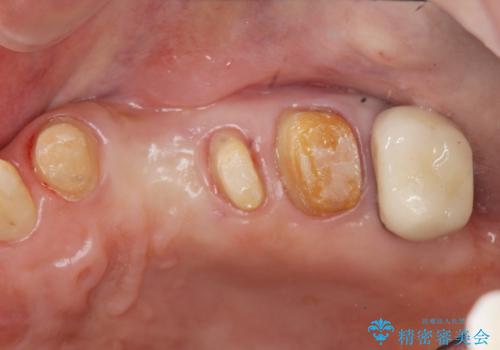

- 全体的に歯が揺れ、このままでは全て歯を失うのではないかと怖くなり歯周病治療を希望され来院されました。

歯列不正による第一小臼歯の骨吸収が認められ、機能咬合力の回復、大きな側方力に連結することで抵抗することのできるブリッジ補綴を選択しました。

歯周病による深いポケット・大きな側方力・短い臨床歯根・欠損の補綴、これらの問題を解決するために歯周補綴を兼ねたブリッジを選択しました。